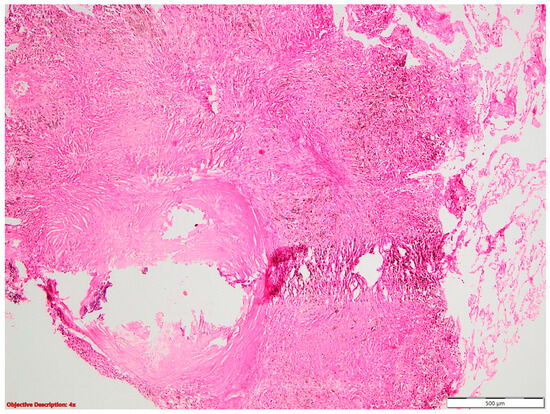

Regarding NSLSC associated with lung infarction (Figure 12), we had four patients in our study, but only for two patients was the lymphovascular invasion microscopically identified. This is a limit of the pathological examination, given the fact that these patients may, in fact, have neoplastic emboli, but these may have not been noticed on the examined slides. Another possible cause of lung infarction may be thrombosis, in the context of neoplastic disease. A Dutch study performed over a period of 7 years, including 3717 patients with lung cancer, highlighted that lung cancer patients had a 6-fold higher likelihood than their cancer-free controls of being hospitalized for pulmonary embolism in the 12 months preceding lung cancer diagnosis [30]. Following diagnosis, lung cancer patients had a 5-fold higher risk of pulmonary embolism in the following 6 months and a 17-fold higher risk in the first 6 months [30]. However, when compared to pulmonary embolism in people without cancer, those with cancer often had less aggressive early clinical symptoms and thrombus burden [31]. These findings highlight the intricate relationship between lung cancer and pulmonary embolism, emphasizing the need for heightened vigilance in identifying and managing thrombotic complications in patients with neoplastic disease. Additionally, they underscore the importance of considering thrombosis as a potential cause of lung infarction in the context of lung cancer.

Figure 12. Lung infarction (→): necrotic alveoli are evident on the left side of the picture; HE, 40×.